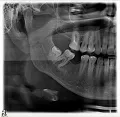

На верхней челюсти справа в районе зуба 6 образовалась небольшая припухлость, которая видна только со стороны щеки, при постукивании на сам зуб отдает болью, десна вокруг зуба не красная и не припухлая, воспаленной не выглядит, зуб залеченный.

Сделали снимок, врач, делавший снимок, направляет на удаление зуба по результатам снимка.

Возможно ли лечение этого зуба?